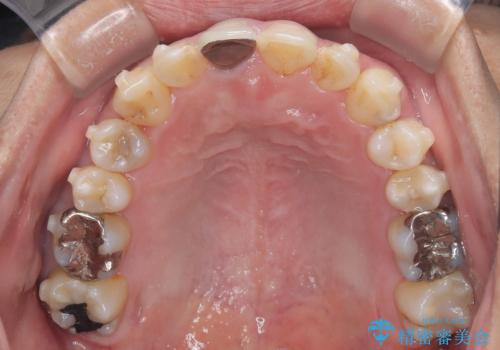

【インビザライン】八重歯と歯のでこぼこが気になる!

- 「八重歯と歯のでこぼこを治したい」を主訴に来院された患者様です。

歯は抜かずに奥歯の遠心移動とIPRで八重歯とでこぼこを改善しました。

左上3番は保険治療(CR)の劣化による二次カリエスになっていますので、後日治療予定です。